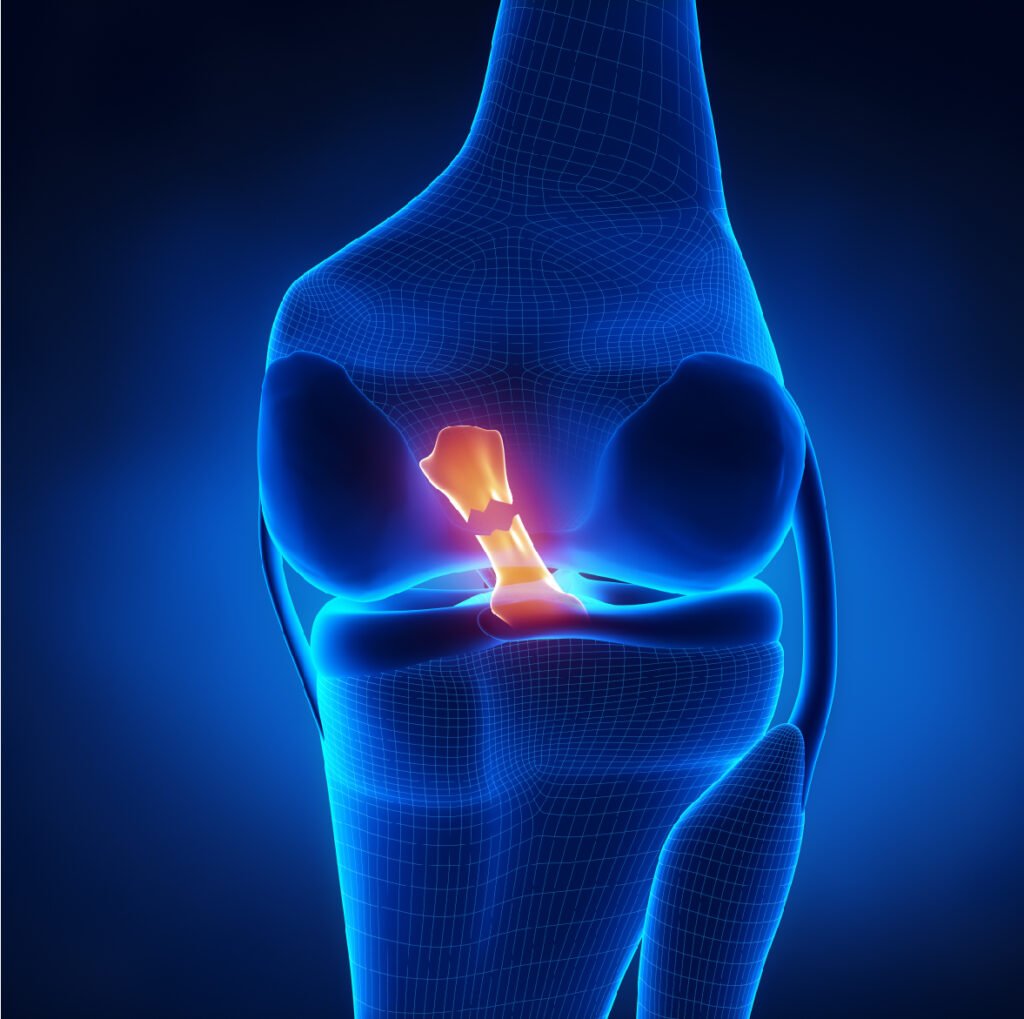

LIGAMENTS CROISÉS

Les ligaments croisés du genou, à savoir le ligament croisé antérieur (LCA) et le ligament croisé postérieur (LCP), jouent un rôle crucial dans la stabilisation de l’articulation du genou, en particulier dans les mouvements de rotation, de translation et de flexion.

Ces deux ligaments sont essentiels pour maintenir la stabilité du genou, surtout lors des activités qui sollicitent fortement l’articulation. Les ruptures de ces ligaments peuvent entraîner une instabilité et nécessitent souvent une prise en charge chirurgicale, notamment pour le LCA, suivie d’une rééducation pour récupérer la fonction du genou.

Le ligament croisé antérieur (LCA) :

Ce ligament se situe à l’avant du genou et empêche la translation antérieure du tibia par rapport au fémur, ainsi que les mouvements excessifs de rotation du genou. Il est particulièrement sollicité lors des activités sportives impliquant des changements rapides de direction, des sauts ou des arrêts brusques. Une rupture du LCA se produit souvent à la suite d’un traumatisme en torsion, comme lors d’un mouvement de pivot ou d’une mauvaise réception après un saut.

Ce type de blessure est fréquent dans des sports comme le football, le basketball, ou le ski.